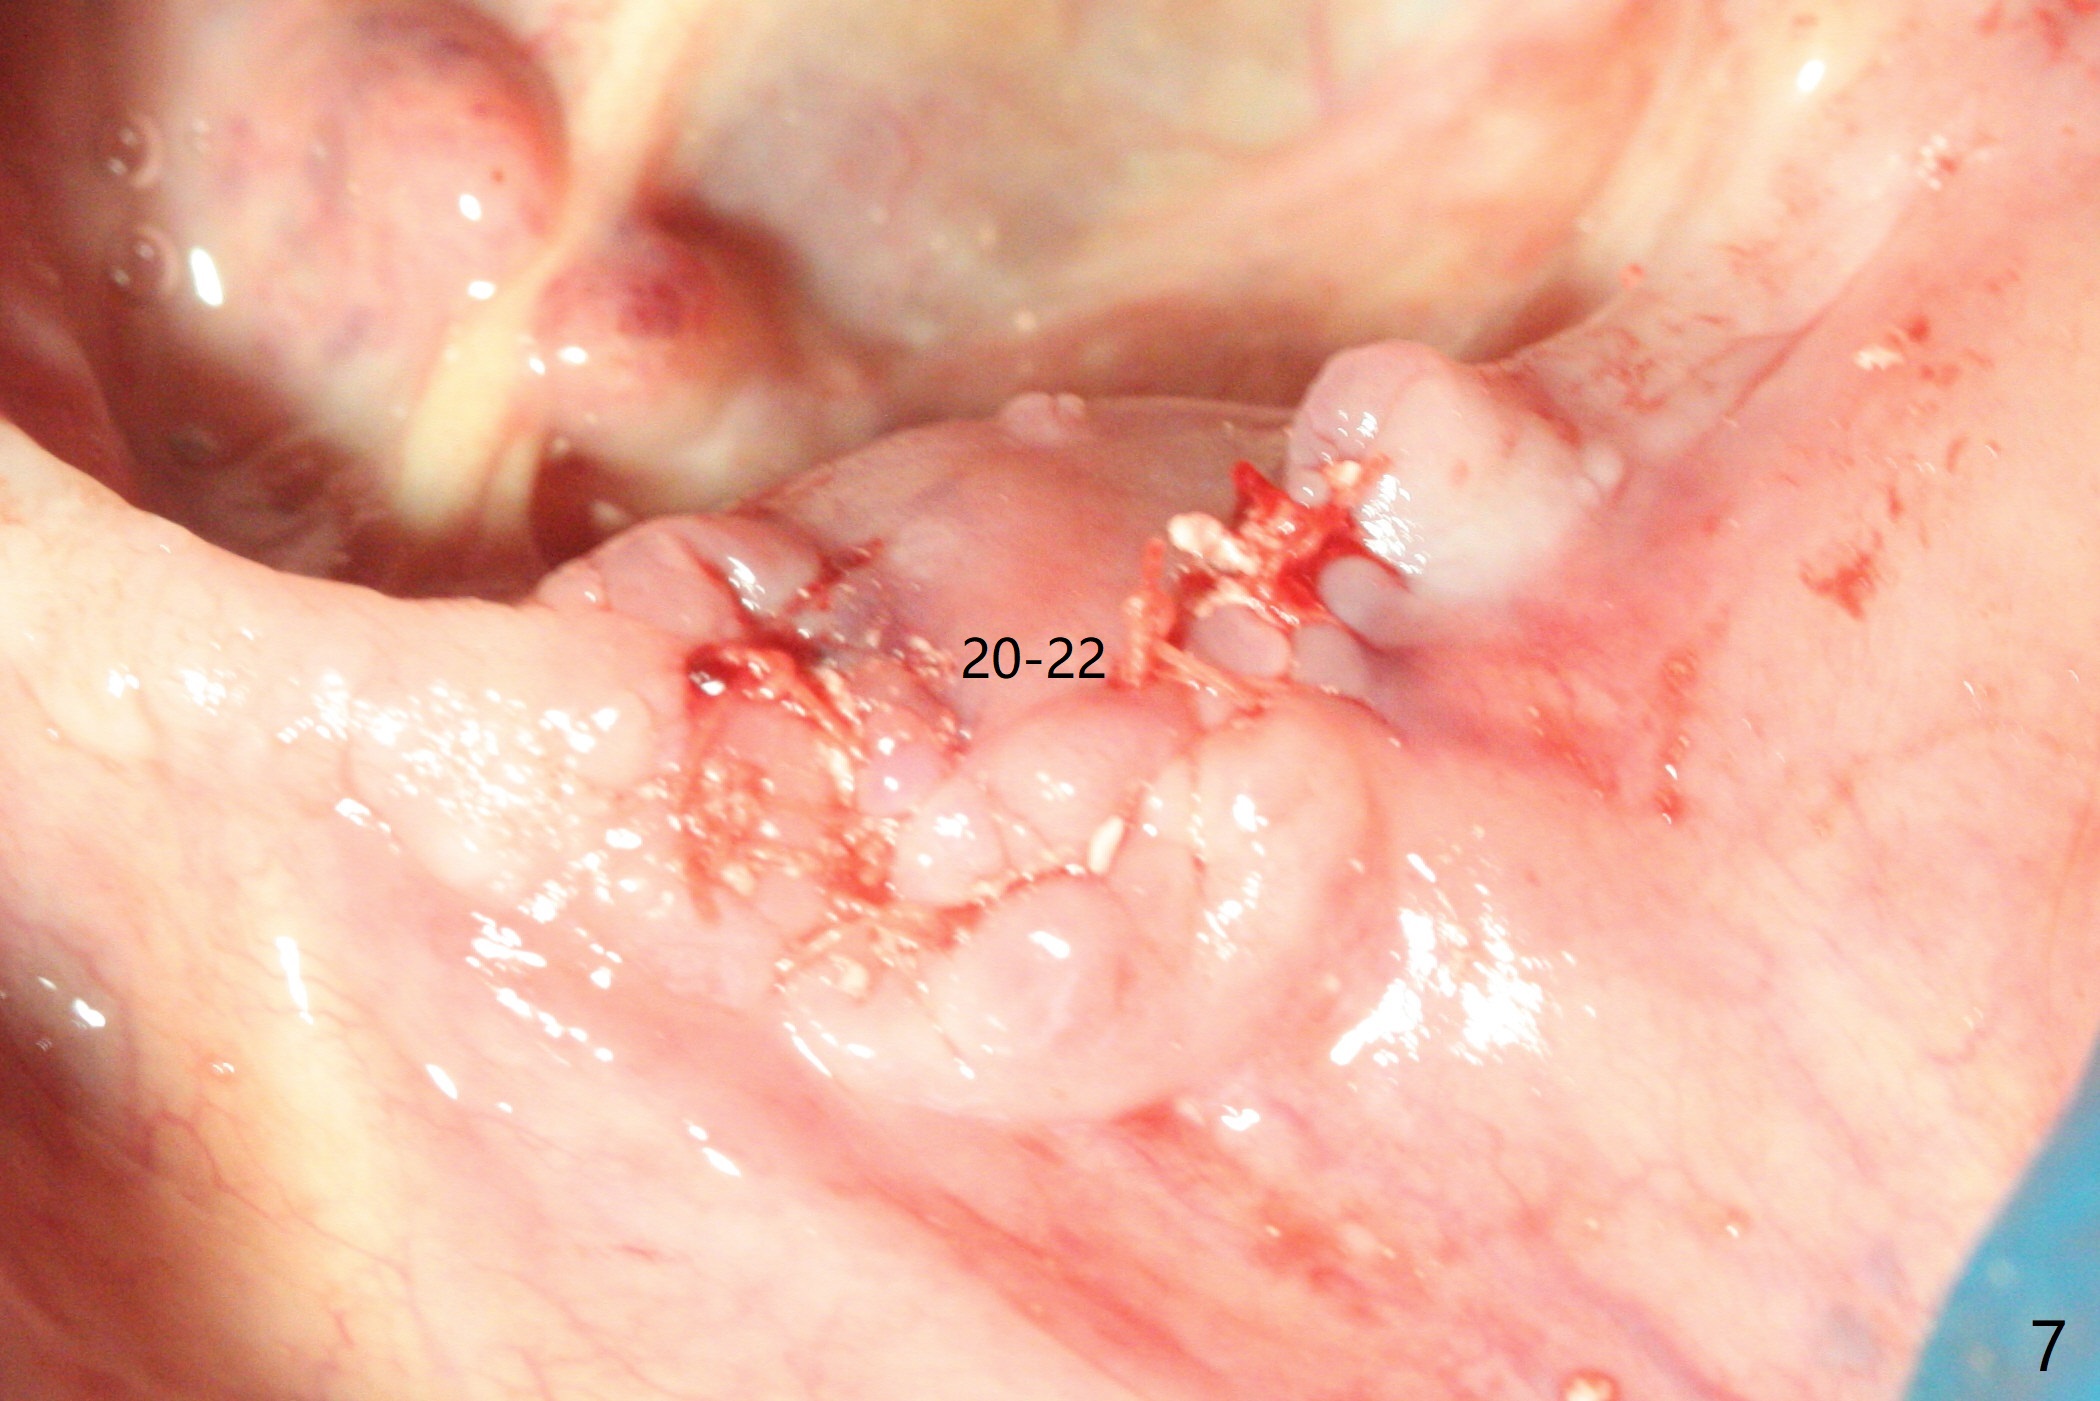

A 84-year-old man (uncontrolled diabetes) requests extraction of terminal teeth (#17, 20-22) for complete denture (Fig.1-3). He does not have finance for implants now. After extraction and debridement, 1 cc of Bond Apatite is applied to the sockets (Fig.4-6). The sockets at #20-22 are primarily closed with 4-0 PGA (Fig.7), while that of #17 with 4-0 Chromic gut suture over Osteogen Plug (a type of Collagen Plug, Fig.8). PGA sutures remain in place (Fig.9,10), while Chromic Gut ones dissolve 7 days postop (Fig.11). The ridge at the extraction sites remains robust 2 months postop (Fig.12). The sockets seem to remain radiopaque 2 months postop (Fig.13).